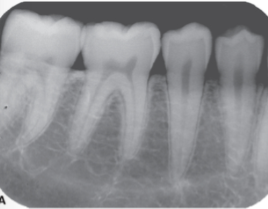

What is happening here

Foreshortening

Insignificant Distortion

Elongation